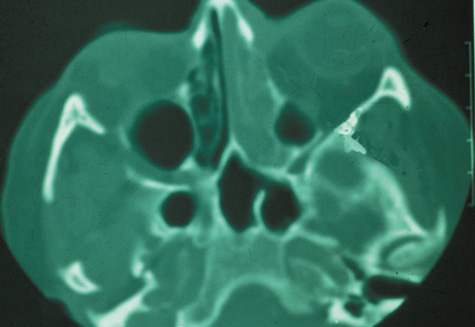

Routine skull films and polytomography have been supplanted by CT in the evaluation of patients with orbital cellulitis.57 CT allows the clinician to differentiate a preseptal cellulitis from an orbital cellulitis.58 If orbital cellulitis has resulted from adjacent intercurrent sinus infection, the diagnosis can be made and the extent of the sinus disease estimated. Sinuses may show changes of osteomyelitis with blurring of the osseous margins of the sinuses, air–fluid levels, or inflammatory tissue within the normally aerated sinus.59 Central nervous system complications can be assessed by neuroimaging, and progression of disease can also be monitored.58

CT should be performed using thin-section (2–4 mm) high-resolution scanning with multiple views of both bone and soft tissue detail.53 Axial and coronal views should be obtained; in one-third of patients with subperiosteal abscesses, the abscess was seen in the coronal sections only.18 Helical CT is a fairly new technology that allows increased resolution with decreased imaging time.60 This type of scan may be especially beneficial in children because of the ability to obtain good imaging with a shorter imaging time.60 elica He HhIntravenous contrast material is not advocated at all centers because there is intrinsically high contrast between infectious changes and orbital fat. However, some authors believe that it is essential to the diagnosis, and it thus remains the preference of the individual clinician, as well as the neuroradiologist.22,59,62

With preseptal inflammation, CT demonstrates soft tissue swelling of the eyelids and tissue adjacent to the orbital septum (Fig. 15). The orbit is not involved, and usually the sinuses do not show evidence of inflammation. The distinction between inflammatory preseptal cellulitis and edema cannot be made.63

Fig. 15. Computed tomography showing preseptal cellulitis of left eye. Note that all swelling is anterior to the orbital septum.